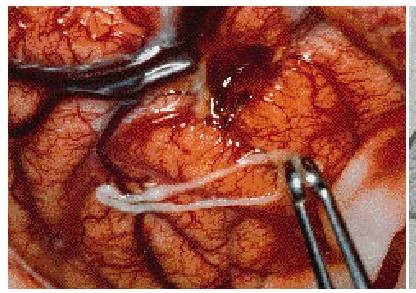

Hình 3: Sparganum được gắp ra từ vỏ não chẩm phải

(Nguồn: https://web.stanford.edu)

Rạch và gắp sparganum ra nhưng thao tác cần nhanh vì ấu trùng có thể di chuyển đi chỗ khác.